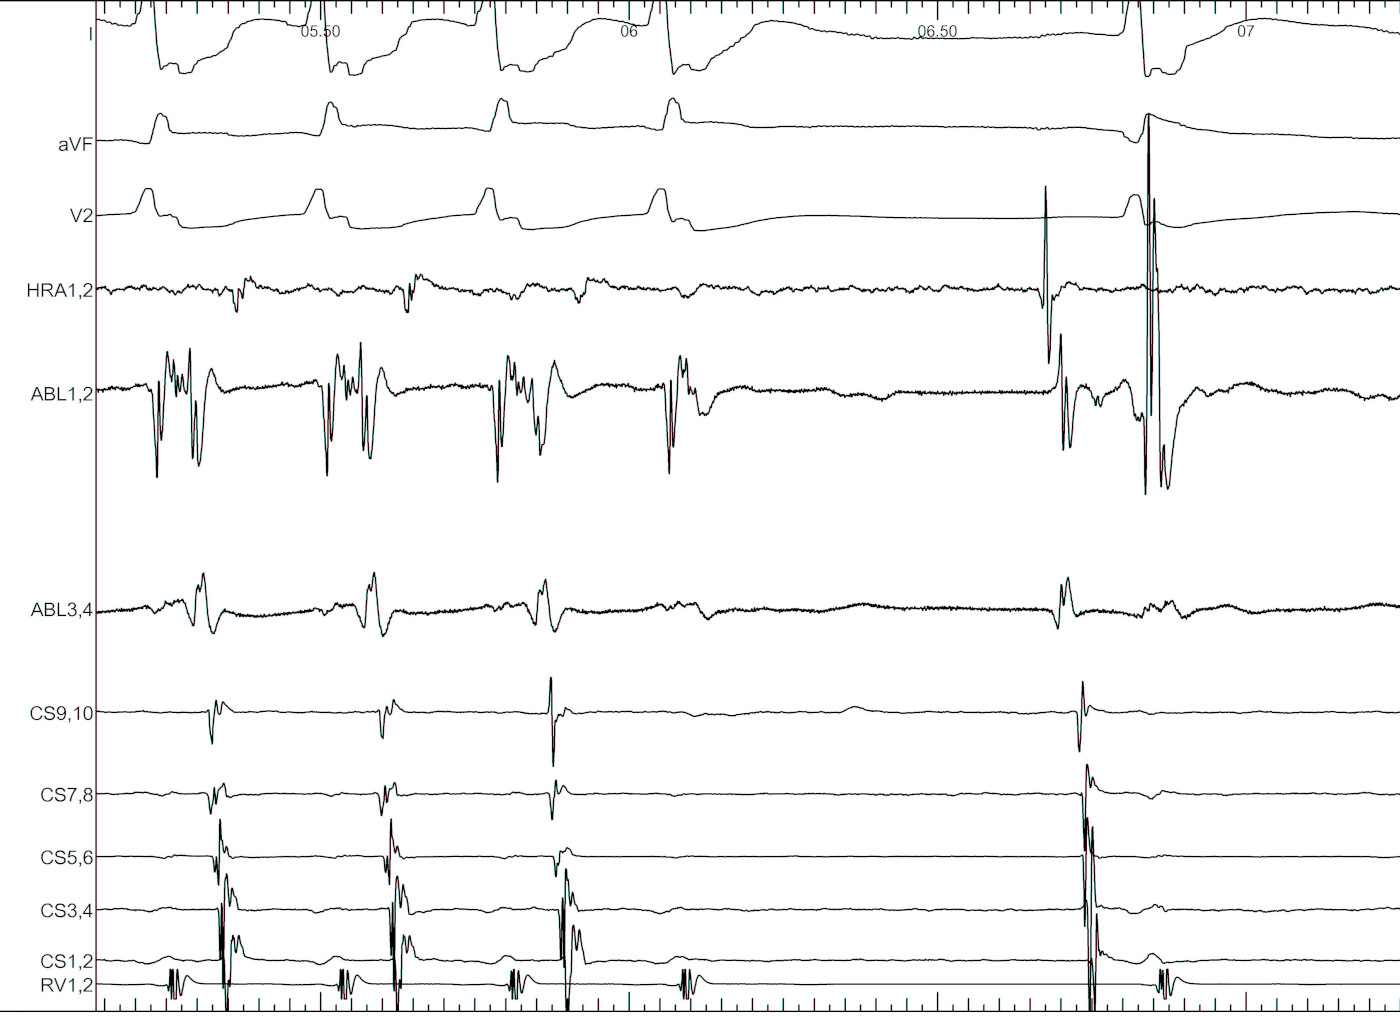

#3 Use triggered mode for mapping

trigger.jpg